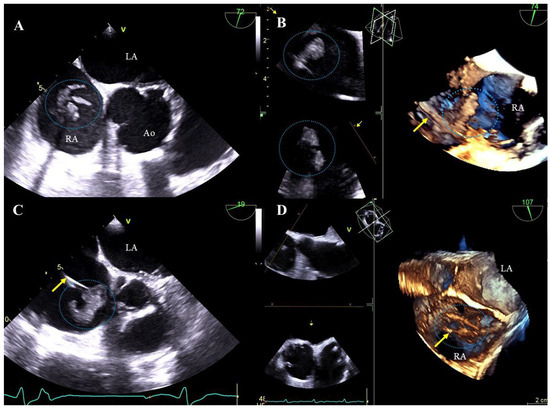

Bacterial vegetations: multi-shaped, irregular, of varying size, balloting formations of heterogeneous echogenicity. Vegetations are diagnosed if there are signs of a generalized infection (positive inflammation markers, blood cultures) or local infection (generator pocket infection) (Figure 2A–D, Movie S4).

Figure 2. TEE images (2D, 3D) showing vegetations on CIED leads. Various-shaped structures representing bacterial vegetations (blue circles) are visualized on the leads (yellow arrow) in the right atrium. D TEE (A,C), 3D TEE (B,D).